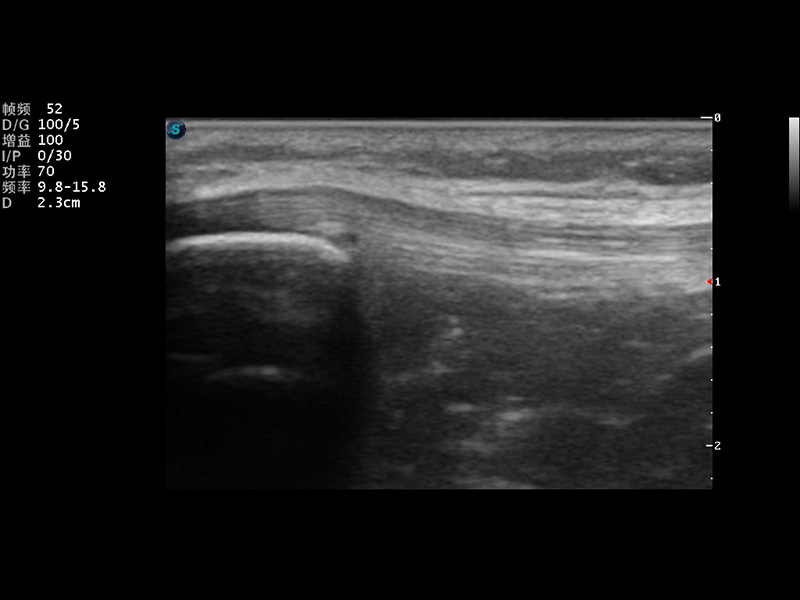

S9便携式彩色多普勒超声诊断仪是银河集团官网研发的高端便携彩超设备,外观设计新颖、产品性能卓越。S9在便携超声领域采用了突破传统的触摸屏交互设计,并以先进的软件硬件技术和设计理念,为您带来清晰的图像质量、稳定的工作性能和便捷的操作体验。